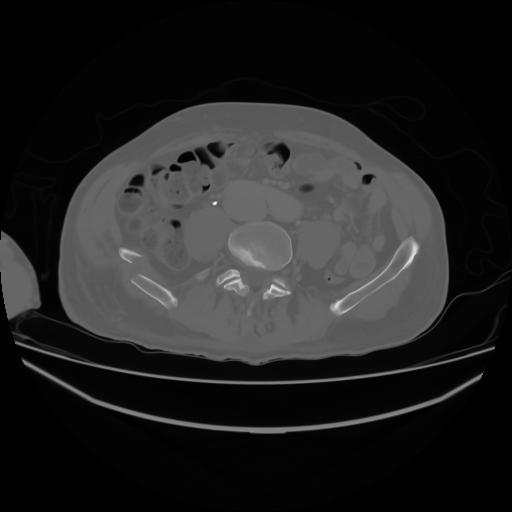

4 CUERPO,CE,Axial,3.0,CUERPO,,